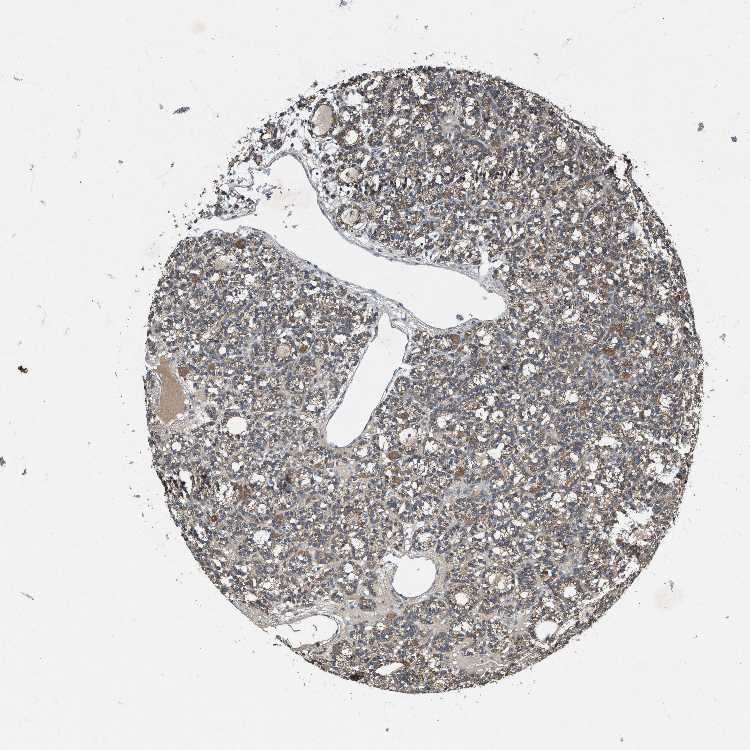

PARATHYROID GLAND - Antibody stainingi

Antibody staining in the annotated cell types in the current human tissue is reported as not detected, low, medium, or high, based on conventional immunohistochemistry profiling in selected tissues. This score is based on the combination of the staining intensity and fraction of stained cells.

Each image is clickable and will lead to virtual microscopy that enables deeper exploration of all samples and also displays staining intensity scores, fraction scores and subcellular localization as well as patient and tissue information for each sample.

Antibody HPA019950

Glandular cells Medium